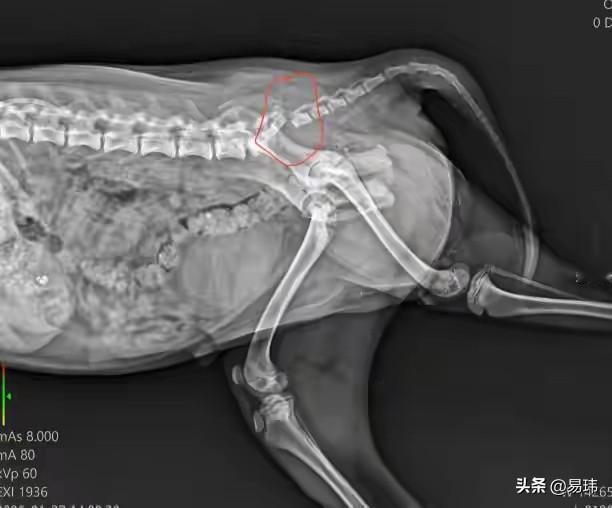

太可怜了,这天一位小姐姐下班回家,当她走到一条小路上的时候,看到路边一只可怜的狗狗奄奄一息的趴在地上,它不停地哀嚎,小姐姐顿时心生怜悯,决定救助这只可怜的狗狗。 善良的小姐姐把它送去了宠物医院治疗,经过拍片发现它的尾巴骨折了,需要做手术并且住院,最终在它出院后,小姐姐把它带回去收养了,相信在她的照顾下,这只狗狗也会越来越好的的。